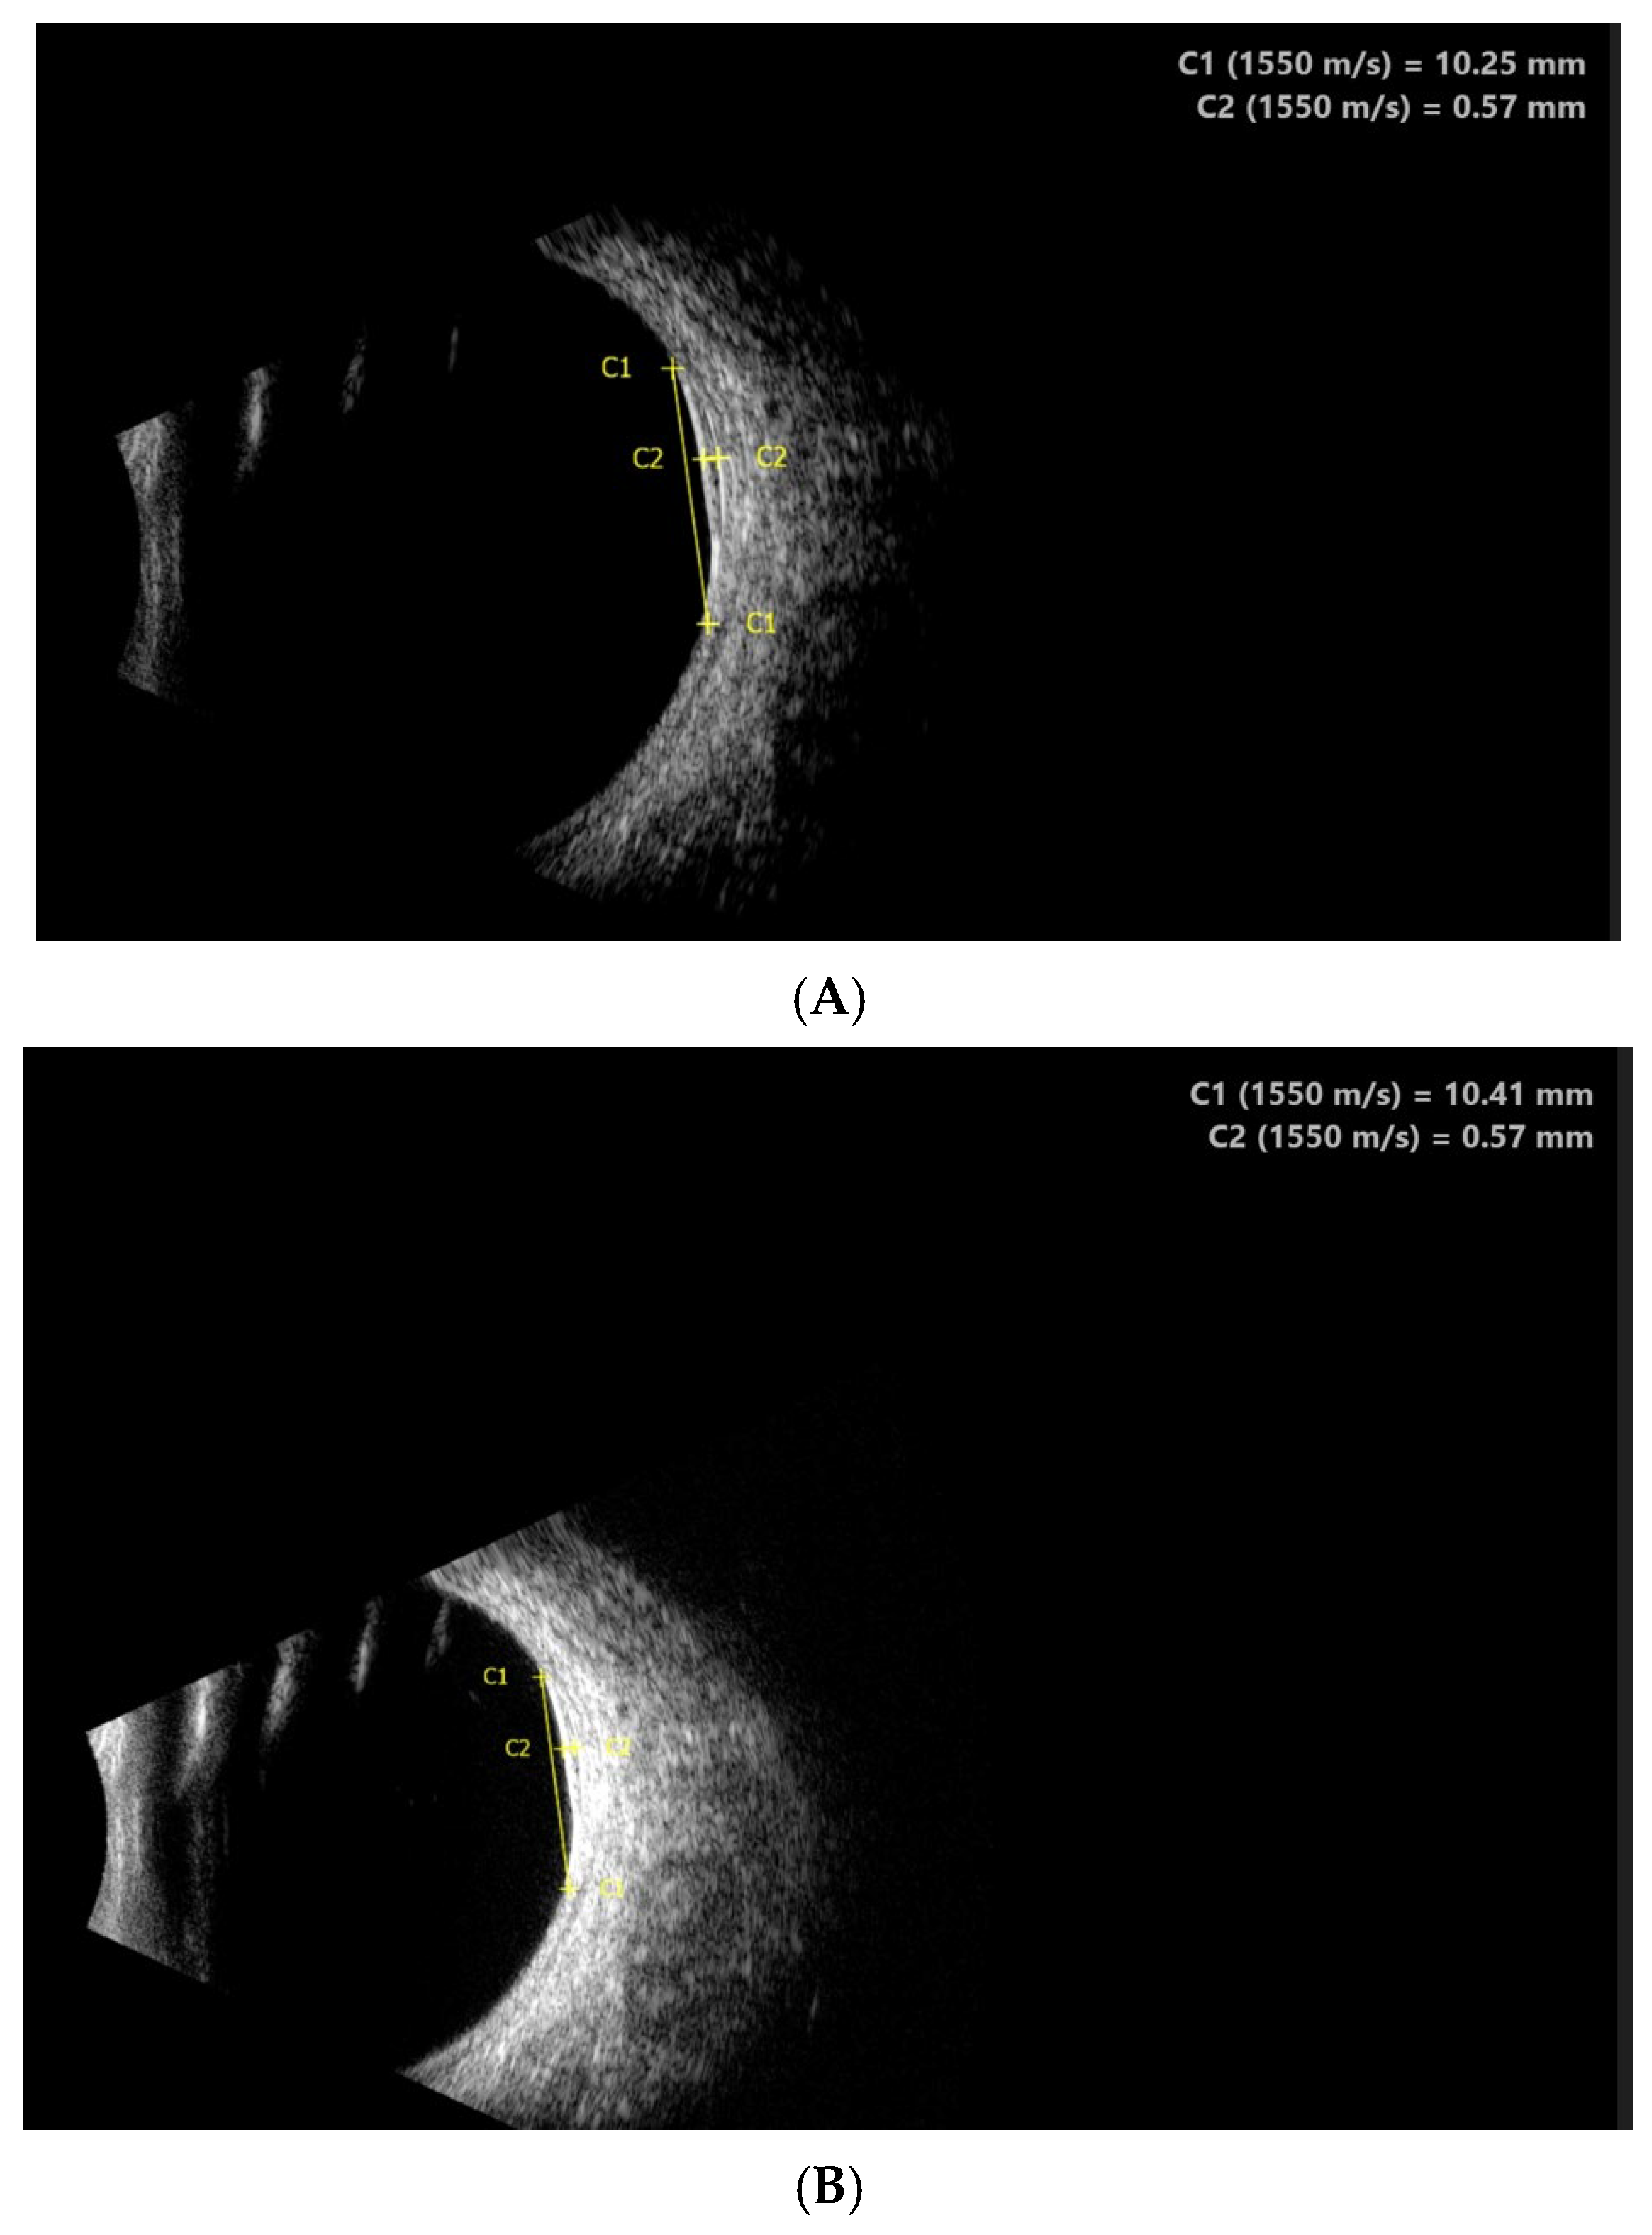

2.2. Clinical Findings

2.3. Diagnostic Assessment